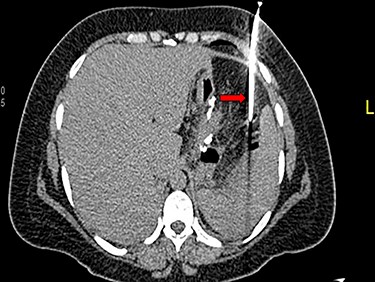

A 36-year-old obese female patient underwent a sleeve gastrectomy abroad. Eleven days after surgery, she presented with an abdominal pain. Abdominal computer tomography (CT) revealed several fluid-air collections (3 abscesses) around the upper greater gastric curve (3.5 × 3.2 cm), lesser sac (7 × 3.3 cm) as well as anterior to the spleen (7 × 3.3 cm). By that time, there was also left pleural effusion and atelectasis of the left lower lung lobe. On the next day, CT-guided aspiration was done (Fig. 1) and a pigtail catheter was inserted to drain the abscesses. On the following day, water-soluble oral contrast displayed an active contrast leak along the proximal sleeve gastrectomy (Fig. 2). On the same day, covered esophageal stent was placed endoscopically. The patient was discharged home and was scheduled for stent removal after 2 weeks. However, after 2 days, the patient presented again with an abdominal pain. The plain x-ray showed slippage of the stent distally. Upper GI endoscopy was done, and the esophageal stent was removed. One day later, the patient condition deteriorated with a massive upper GI bleeding. A CT angiography showed no extravasation and the source of bleeding was not identified during endoscopy due to massive bleeding. An immediately performed angiogram revealed an AEF (Fig. 3). The interventional radiologist achieved transient cessation of the bleeding through embolization of the fistula with interlock coils (Fig. 3). An aortogram showed continuous extravasation of contrast through the fistula, and therefore, endovascular intervention was performed with implantation of 22 mm × 112 mm aortic stent (TEVAR using Valiant covered stent - Medtronic company, USA). One week after TEVAR, another long esophageal stent was positioned (from lower esophagus to the stomach). Two weeks later, a barium swallow proved no evidence of contrast leak. Then, the esophageal stent was removed, and the patient was discharged home. There was a plan for definitive reconstruction procedure, including removal of the endovascular stent and use of reconstructed pericardial bovine graft, however, the patient declined. About 10 months later, she presented with another attack of massive hematemesis, with a drop of hemoglobin to 8 g/dl and a blood pressure of 66/44 mmHg requiring a rapid sequence induction and infusion of packed red blood cells. An immediate abdominal CT showed evidence of peri-stent infection with no contrast extravasation. Upper GI endoscopy showed an evidence of an ischemic ulcer above the Z-line with granulation tissue at the ulcer edge and erosion of the endovascular stent into the lower esophagus. The patient had a positron emission tomography (PET) scan and diagnosed with mediastinitis due to aortic stent infection and septic shock (Fig. 4). Surgical intervention was offered but the patient declined. Treatment with broad spectrum antibiotics and blood transfusion were administrated as required. Around 5 weeks later, the patient developed massive upper GI bleeding requiring intubation and surgical intervention (distal esophagectomy with removal of the endovascular stent and resection and replacement of the AEF site with reconstructed tube using 14 × 9 cm bovine pericardial graft through left thoraco-abdominal incision utilizing left cardiopulmonary bypass and distal perfusion through left femoral artery (Fig. 5). Closure of the stomach with gastrostomy tube insertion for feeding had been performed. One and half year later, reconstruction surgery of the esophagus with colonic interposition was done. After 3-year follow-up, the patient was doing well with no complication.

(A) Oral contrast medium showing communication between the lower esophagus and the site of collection drained by percutaneous pigtail catheter. (B) Distal esophageal stent was placed to cover the site of fistula. (C) No contrast extravasation.